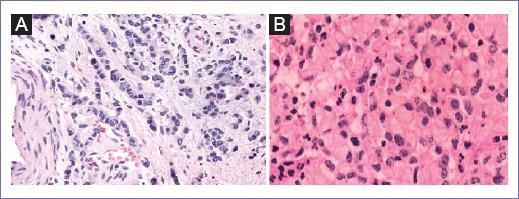

Al descartar un origen metastásico, se hace diagnóstico de un adenocarcinoma de células en anillo de sello primario de cérvix y se maneja mediante histerectomía radical Querleu-Morrow tipo C1 con linfadenectomía pélvica bilateral y muestreo ganglionar periaórtico. Con reporte histopatológico definitivo de: adenocarcinoma poco diferenciado con células en anillo de sello de 4.5 cm en su eje mayor, rodete vaginal sin lesión tumoral, parametrios sin neoplasia, endometrio con atrofia. Linfa pélvica derecha con seis ganglios con hiperplasia mixta, linfa pélvica izquierda con 12 ganglios con hiperplasia mixta y linfa periaórtica con tres ganglios con hiperplasia mixta (Fig. 6).

Figura 6 A: fotomicrografía (40x) de la sección teñida con hematoxilina y eosina (H-E) del cuello uterino que muestra una neoplasia epitelial maligna con patrón de crecimiento difuso y en hileras. B: fotomicrografía (40x) de corte teñido con H-E que muestra células neoplásicas poligonales con citoplasma vacuolado y rechazo del núcleo hipercromático a la periferia, característico de las células en anillo de sello.

Histológicamente las características más notables que apoyan el origen primario en cérvix de la lesión son la ausencia de reacción desmoplásica y la presencia de células en anillo de sello con cantidades abundantes de mucina. Además, se debe descartar la positividad de marcadores de inmunohistoquímica que sugieran un origen primario de mama (citoqueratina [CK] 7, receptor de estrógeno, receptor de progesterona, GCDFP15 [gross cystic disease fluid protein 15] y mamoglobina), así como marcadores que sugieran un origen intestinal (ACE, CK20 y proteína caudal homeobox 2)10.